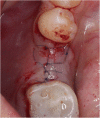

Methods: After randomization, 31 fully threaded titanium implants were inserted in 31 patients (16 men and 15 women) in the lower mandible using a split-flap technique. In the test group (10 patients), mucosa was treated with a PRF membrane. In the control group (21 patients), implantation was realized without soft tissue augmentation. Tissue thickness was measured at point of implant insertion (baseline) and at time of reentry after 3 months. Standardized digital radiographs were obtained for evaluation at time of implant placement, reentry after 3 months and at a 6-month follow-up. Data was analyzed by an independent examiner.

Results: After 6 months, all 31 implants were osteointegrated. Soft tissue augmentation with PRF led to a significant tissue loss. In the test group, the crestal tissue thickness dropped from 2.20 mm ± 0.48 SD at baseline to 0.9 mm ± 1.02 SD at reentry, whereas crestal mucosa in the control group showed higher stability (2.64 mm ± 0.48 SD at baseline to 2.62 mm ± 0.61 SD at reentry). For ethical reasons, the test group was terminated after 10 cases, and the remaining cases were finished within the control group. In the test group, radiographic evaluation showed a mean bone loss of 0.77 mm ± 0.42 SD/0.57 mm ± 0.44 SD (defect depth/defect width) on the mesial side and 0.82 mm ± 0.42 SD/0.62 mm ± 0.36 SD (defect depth/defect width) on the distal side. In the control group, a mean bone loss of 0.72 mm ± 0.61 SD/0.51 mm ± 0.48 mm (defect depth/defect width) on the mesial and 0.82 mm ± 0.77 SD/ 0.57 mm ± 0.58 SD (defect depth /defect width) on the distal side was measured.